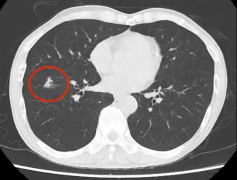

胸部CT常见的影像表现及对应的诊断要点环医疗3- 环医疗腺样体肥大到底要不要切?请看这里→

- 环医疗胸部CT常见的影像表现及对应的诊断要点